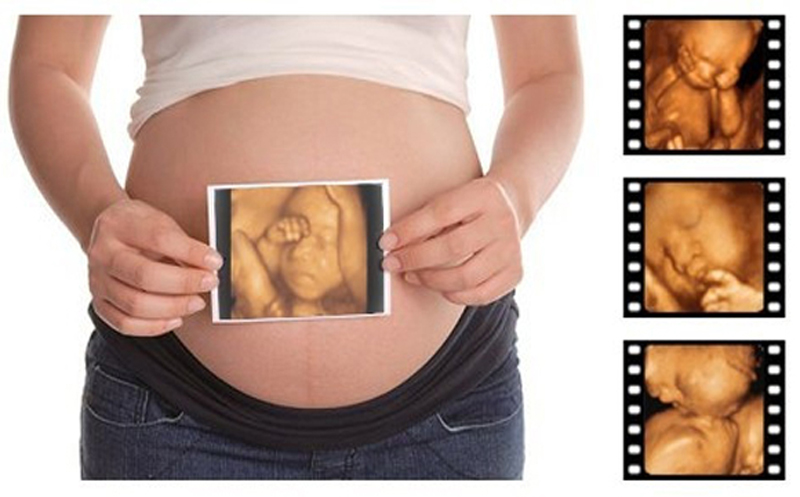

准妈妈们都会关心自己的宝宝出生后好不好看,和孕期的四维照片像不像,所以都会问医生:准妈妈们在孕期给宝宝照的四维照片和宝宝刚出生的时候会很像吗?下面是有关人士给的回答,大家可以一起来看看。

医生会说像,胎宝宝在6、7个月的时候各方面已经基本发育成熟了,在孕后期汲取的营养主要用来长肉长身体以及长脂肪了,只要四维照够清晰,就是孩子出生后的样子了。其实胎儿的四维照和宝宝出生后的基本轮廓是像的。

伴随着孩子的长大,孩子现在两岁了,大家都说这个孩子长的越来越像妈妈了,特备是脸型以及下巴。所以说四维可能并不是反映宝宝在刚出生的时候的样子,而是长大以后的相貌以及特征。

由此可见,宝宝照四维时的照片可能和宝宝刚出生时是不像的,但是四维主要是要看清宝宝的骨骼发育是否健康,即使是刚出生的时候与四维不像,慢慢长大以后是会越来越在照四维时的长相。